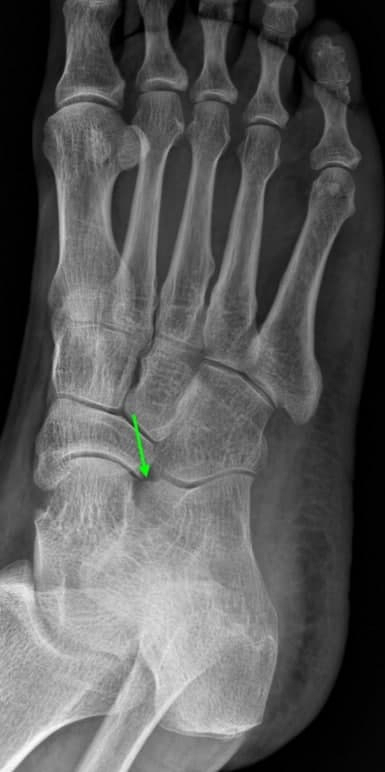

위 환자분은 오전 10시경 화곡역 계단에서 발목을 접질린 후 발등 통증으로 정형외과에서 X-ray 검사를 받으셨습니다. 담당 전문의 선생님께서 X선 판독을 보시고는 뼈는 괜찮고 인대가 늘어났다고 진통소염제를 처방해주셨습니다. 원래 다른 부위를 치료받던 환자분이라 영상CD를 복사하여 11시쯤 바로 한의원으로 걸어서 내원하셨습니다.

## 엑스레이를 꼼꼼하게 살펴보니 골절선이 명확하게 보이지 않았습니다.환자분의 발목에서 부어있는 곳을 2mm단위로 바둑판처럼 촘촘하게 하나 하나 눌러서 아픈 부위를 찾아봤습니다. 환자분께서 통증을 호소하는 곳은 종골이라는 뼈의 앞쪽 돌기였습니다. 발목을 접질렀을때 인대가 늘어나면서 파열도 잘 생기는 곳이고, 뼈를 잡아당기면서 골절도 자주 생기는 부위입니다. ## 무엇보다 제일 큰 문제는 종골 전방돌기가 엑스레이상 뼈가 겹쳐보여서 실금(미세골절), 견열골절이 잘 보이지 않는다는 것입니다. 걷는데 큰 지장이 없고, 인대를 늘려봤을 때 많이 아프지 않다고 하셔서 미세골절 가능성을 충분히 설명해드리고 MRI보다 CT 검사를 권고 드렸습니다. ## 작은 뼈 조각은 MRI에서 보이지 않기 때문에 뼈를 위주로 관찰하는 CT 검사가 골절 진단에 더 적합합니다. 만약 걷기가 어렵고 스트레스 검사상 통증이 심하다면 주변 인대, 근육, 연골 손상이나 뼈에 멍이 드는 골수 부종도 있을 수 있어 MRI 검사를 같이 실시해야 합니다. 어떤 검사를 하면 좋을지는 의학적 전문지식이 필요한 영역으로 진료의가 결정해드립니다..그러니까 크게 고민하지 않으셔도 괜찮습니다.

골절의 가능성이 있으므로 비탄력 테이핑으로 발목을 단단하게 고정하고 협력병원으로 즉시 CT검사를 의뢰하였습니다. ## X-ray를 찍은지 2시간 뒤인 12시반쯤 시행한 CT검사에서 종골 전방돌기의 골절로 진단되었습니다.

위 사진처럼 발등 골절이 좌측 X-ray에서 보이지 않았지만, 우측 CT에서는 보입니다.초기 미세골절, 견열골절, 실금은 단순 방사선 검사인 엑스레이에서 잘 보이지 않습니다.그렇다고 CT가 완전한 골절 진단법일까요?아닙니다. 연식이 오래된 예전 CT 검사에서는 2mm 이하의 작은 뼈 조각은 안 보일 때도 있습니다. 그래서 가급적 최신 640 CT나 초음파검사로 골절 의심부위를 촘촘하게 단면을 확인해보는 것이 좋습니다.**